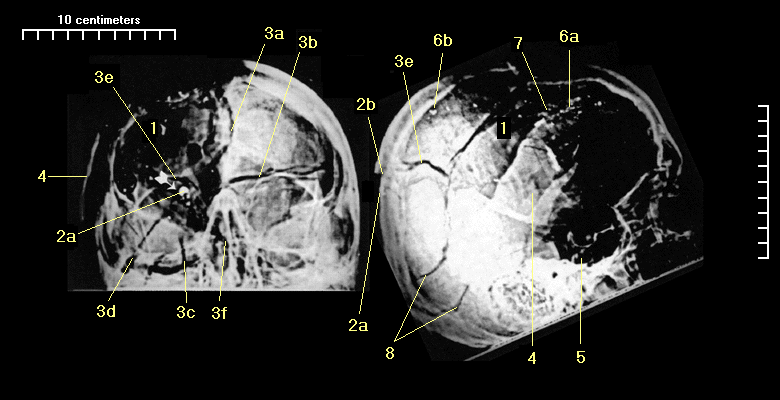

I assembled a list of features noted by the HSCA radiologists in their reports. I numbered the list and located the features on the X-rays to the best of my ability. At the bottom of the page are labeled frontal and lateral skull models for reference.

| 1. | GM: Nearly complete loss of right parietal bone, the upper portion of the right temporal bone, and a portion of the posterior aspect of the right frontal bone. DD: .there is apparently absence of bone anterior to this line, with the absence present to a point approximately equivalent to where the coronal suture on the right side should be. |

| 2a. | GM: A metallic fragment on the outer table of the right occipital bone 9.6 cm. above the mid portion of the external occipital protuberance (EOP). DD: There is a metallic fragment about 9 or 10cm above the external occipital protuberance, which metallic fragment is apparently imbedded in the outer table of the skull. On the frontal view, this metallic fragment is located 2.5cm to the right of midline, and on the lateral view, it is approximately 3-4cm above the lambda. |

| 2b. | GM: 1 cm. above the metallic fragment is a depressed fracture from which stellate type fractures "radiate" into both occipital bones, the right parietal bone and the right temporal bone. |

| 3. | DD: There are a large number of fractures in the calvarium, and the linear fractures seem to more or less emanate from the imbedded metallic fragment, and radiate in a stellate fashion in various directions. |

| 3a. | DD: There is a large fracture extending directly anteriorly along the sagittal suture, which is, at least at the point visualized, widely separated. This fracture seems to extend into the frontal bone, more or less at the midline, down to the frontal sinus which is also fractured. GM: There are fracture lines through the anterior and posterior aspects of the right frontal sinus with air in this sinus. There is a metallic fragment above the sinus appearing to be between the bony tables of the frontal bone. |

| 3b. | DD: There is a sharply defined linear fracture extending laterally from the metallic fragment into the left side of the calvarium, around the parietal bone to the lateral aspect of the skull. |

| 3c. | DD: Two linear fractures extend inferolaterally from the metallic fragment, one into the occipital bone, about 3cm from the midline, and this fracture crosses the lambdoid suture. |

| 3d. | DD: The other one is more lateral, and extends down toward the lateral sinus, probably above the lambdoid suture. |

| 3e. | DD: Additionally, there is a fracture line extending more or less laterally from the metallic fragment toward the temporal bone on the right side, which is identified only by the anterior edge of the posterior fragment, since there is apparently absence of bone anterior to this line, with the absence present to a point approximately equivalent to where the coronal suture on the right side should be. |

| 3f. | DD: I neglected to describe in the text of this report an extensive fracture which extends inferolaterally from the impact point toward the left side which probably reaches the temporal bone or at least the mastoid region after crossing a goodly portion of the occipital bone there. |

| 4. | DD: There is a fracture fragment inferior to the absent bone, with the corner of the fragment extending down to the parietal squamosal suture, and this fragment is displaced from its normal position as indicated by overlap of the infero and posterior aspects of the fracture fragment. |

| 5. | GM: There is a fracture line extending through the floor of the sella turcica with bony fragments in the sphenoid sinus. |

| 6a. | GM: A linear alignment of tiny metallic fragments is associated with the entry, path travel, and exit in the posterior aspect of the right frontal bone. |

| 6b. | DD: There are a number of metallic fragments extending anteriorly from the inner table of the skull at a point approximately 6cm antero-superiorly from the previously described imbedded metallic fragment. These fragments extend inferoanteriorly across the entire skull and actually project (on other images that I have seen) in a fashion that suggests that the the large fragment is outside the intracranial space. Presumably this represents a metallic fragment in the scalp, although this cannot be accurately determined from this particular examination. |

| 7. | DD: It also seems reasonable to assume that the exit point is near the coronal suture on the right side, about 5 or 6, or perhaps slightly more, cm above the pterion. |

| 8. | RR: This fracture pattern is discussed in a paper by Smith, et al. In the JOURNAL OF FORENSIC SCIENCES 1987.in which they explain how acutely increased internal pressure during a projectile injury produces concentric heaving fractures. |